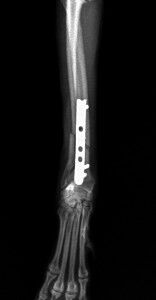

手術後1か月は外固定で補助します。その後、レントゲンで問題ないことを確認し外固定を外しました。外した後は普通に歩行し、散歩なども普段通りにしてもらいます。獣医師によってはプレートを残したままにすることがありますが、中にはプレート部分の骨が細くなってしまうことがあります。もし仮にプレートが折れてしまった時には大変な手術が必要になることがあります。当院では高齢犬であればプレートを残したままにするのですが、この症例は若かったので上記の心配もありますので、プレートを除去することにしました。ただトイ・プードルは骨の増生が良くないことが多いので、プレートを外した直後に再骨折したということがよくあります。ですので、当院ではプレートを留めているスクリューを段階的に外していきます。下の写真は手術後3か月の時に一部のスクリューを取った写真です。

スクリュー除去前 骨折面は消えています。

スクリュー除去後